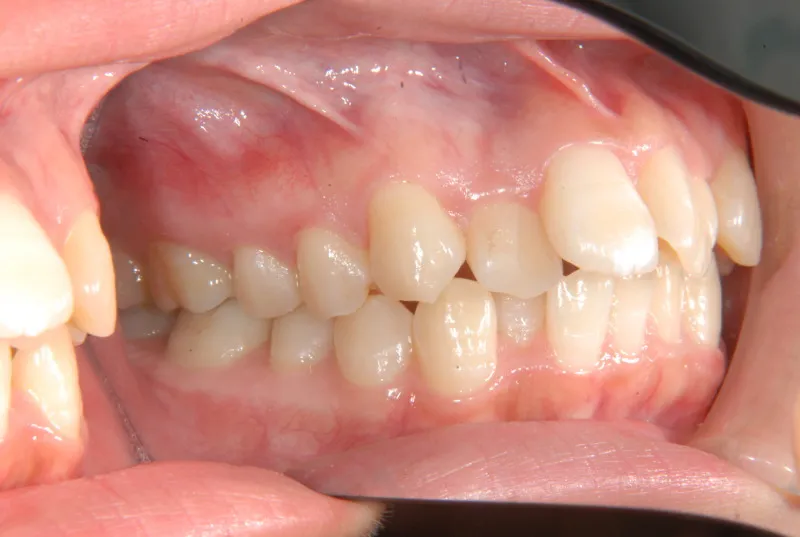

初診時年齢 19~29歳 (女性) 主訴 ガタガタ・90度ねじれている

診断名 叢生・上顎前突 装置名

奥歯が内側と前方にかたむき上下の歯がガタガタに生えています。

90度ねじれた歯もあります。前歯も出っ歯になっています。

歯は抜かず、歯科矯正用アンカースクリューを用いて治療しました。

治療回数○回、2年9ヶ月の治療期間で矯正治療を終了しました。